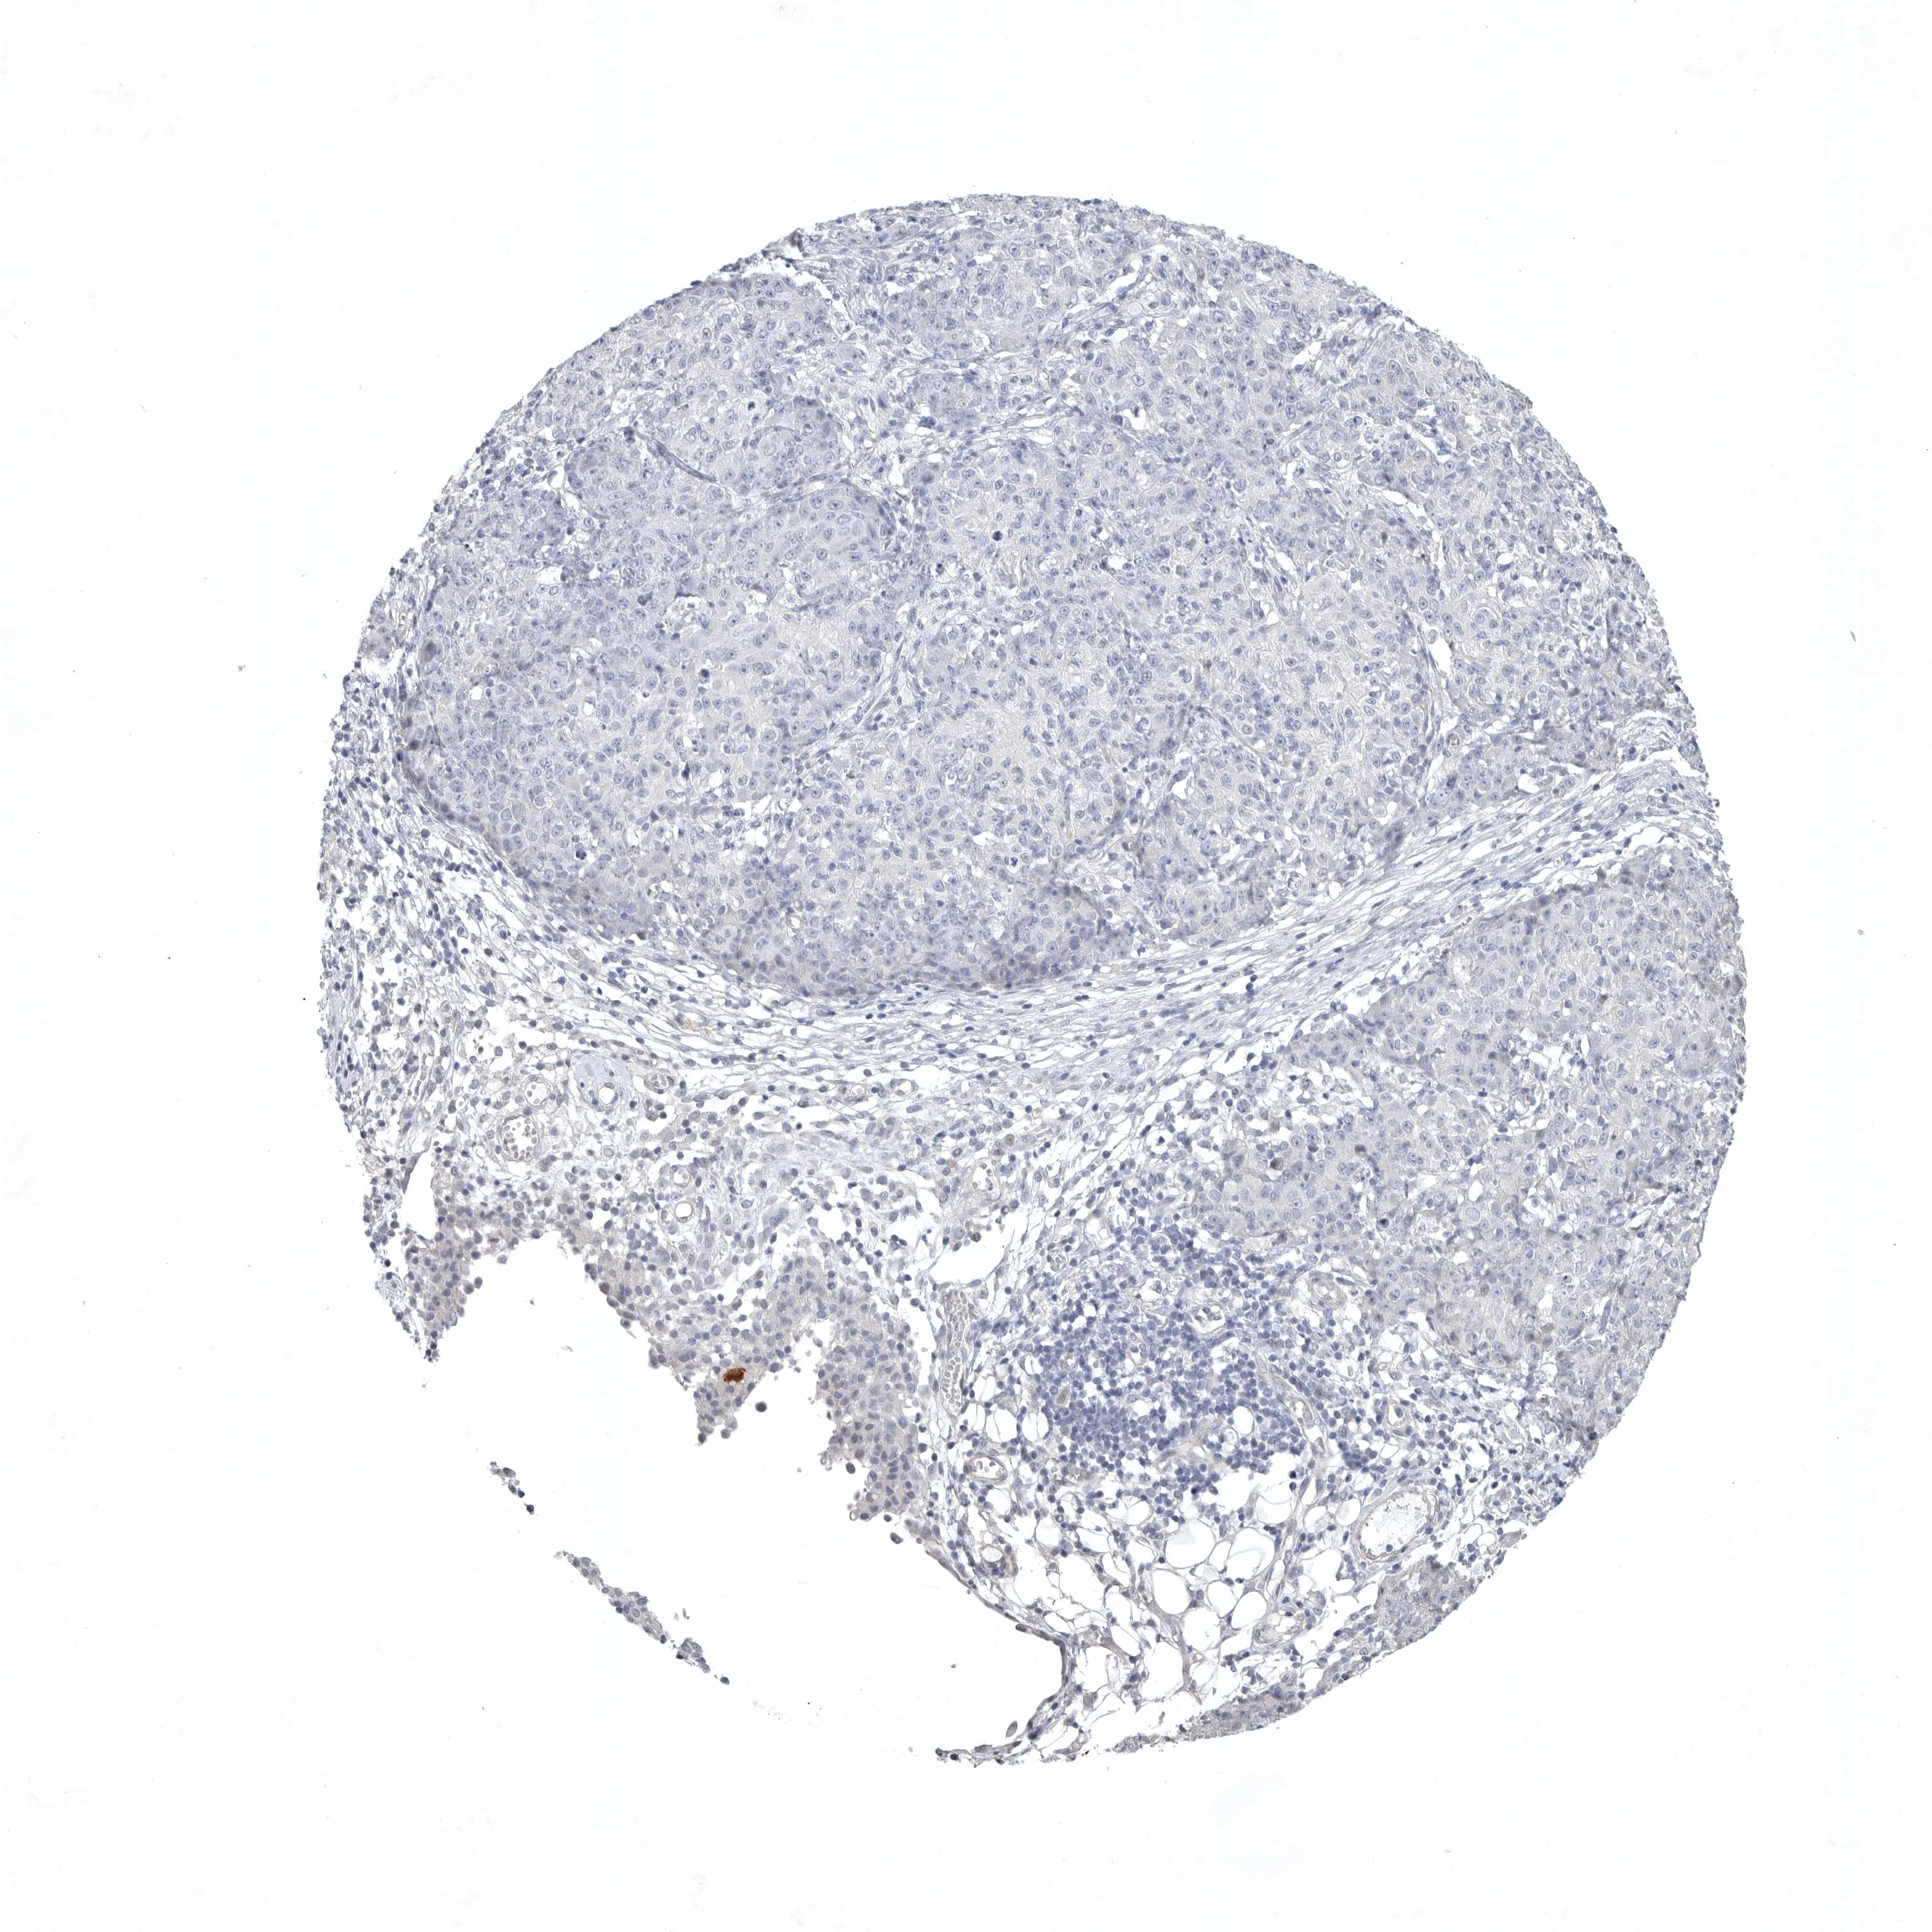

OVARIAN CANCER - Protein expressioni

A mouse-over function shows sample information and annotation data. Click on an image to view it in a full screen mode. Samples can be filtered based on level of antibody staining by selecting one or several of the following categories: high, medium, low and not detected. The assay and annotation is described here.

Note that samples used for immunohistochemistry by the Human Protein Atlas do not correspond to samples in the TCGA dataset.

Antibody stainingi

Antibody staining in the annotated cell types in the current human tissue is reported as not detected, low, medium, or high, based on conventional immunohistochemistry profiling in selected tissues. This score is based on the combination of the staining intensity and fraction of stained cells.

Each image is clickable and will lead to virtual microscopy that enables deeper exploration of all samples and also displays staining intensity scores, fraction scores and subcellular localization as well as patient and tissue information for each sample.

Antibody HPA027134

Antibody HPA027150

Antibody HPA029859

Antibody CAB022343

Cystadenocarcinoma, serous, NOS

Carcinoma, endometroid

Cystadenocarcinoma, mucinous, NOS

Carcinoma, NOS